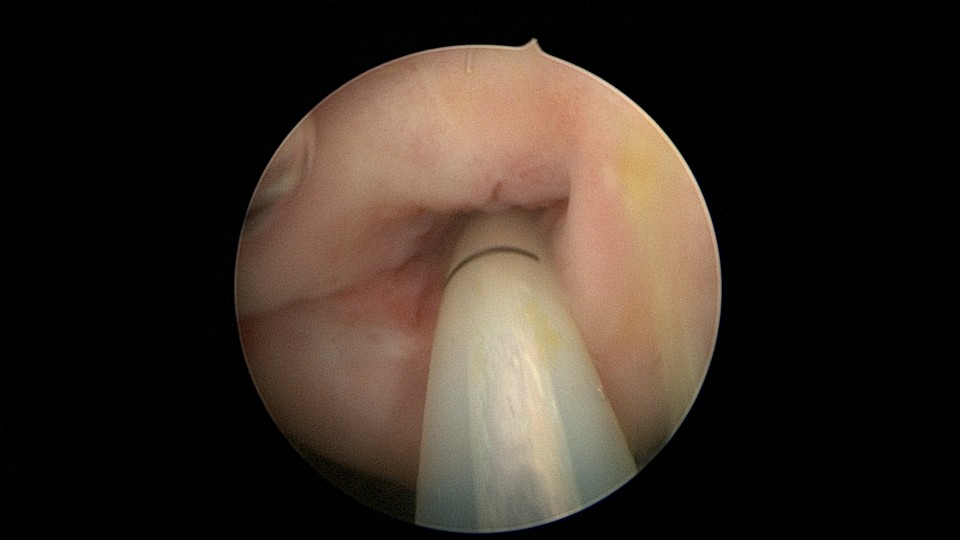

患者33岁,G5P2,顺产2次,胎停清宫后月经量减少,外院B超提示宫腔粘连。2021年5月宫腔镜探查,宫腔重度粘连,宫腔狭小,右侧输卵管开口可见,左侧输卵管开口未见,单极电针分粘,恢复宫腔形态,显露左侧输卵管开口(僵硬)。2021年6月宫腔镜二探取球囊,宫腔形态正常,双侧输卵管开口可见,宫内膜薄。2022年7月自然妊娠,2023年3月孕39+周顺产分娩。现38岁,G6P3,顺产3次。